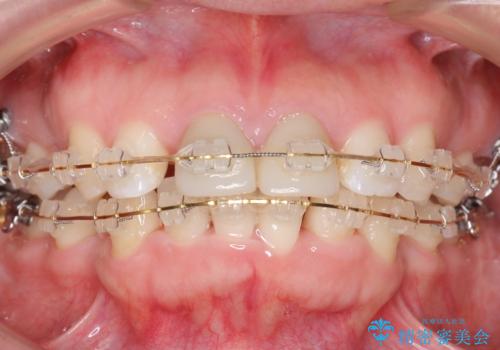

治療途中

-

矯正治療前に、一旦、引っ込めた前歯の角度を元に戻してから(出っ歯の仮歯をもう一度つけました・・・!)矯正しました。